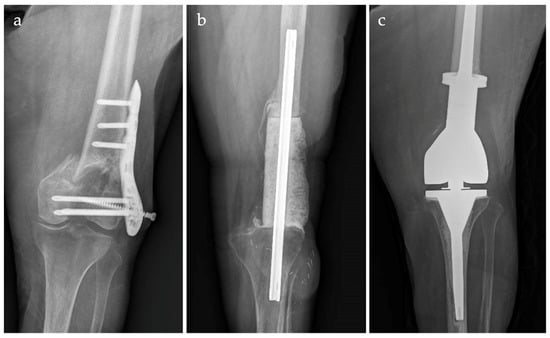

Silver-Coated Distal Femur Megaprosthesis in Chronic Infections with Severe Bone Loss: A Multicentre Case Series

3. Results